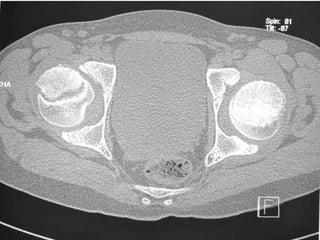

 CT SCAN-

Accurately measures extent of epiphyseal displacement & angulation.